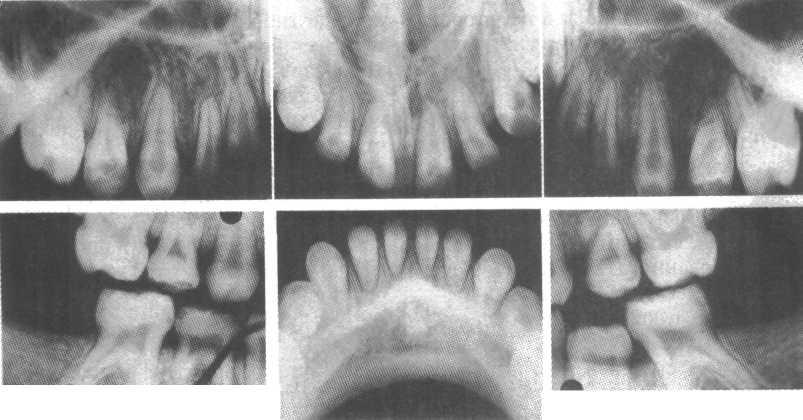

Стоматологические Исследования: Рентген Инвагинации Зубов